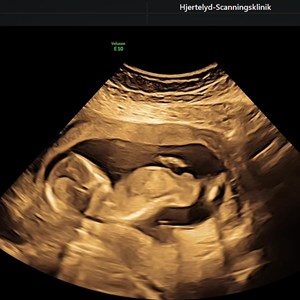

Tænkte det var tid til en lille hygge post 🙂🙃 Denne lille uge 15 baby spræller så fint ...

MODERKAGE PÅ FORVÆG ? Mange tror, at det bliver ekstra svært at få fine 3D billeder af ba...